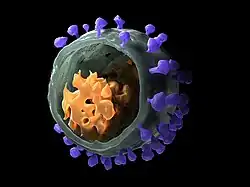

| SIV virion model obtained with cryo-electron microscopy scanning | |

The SIV virion is a spherical to pleomorphic glycoprotein envelope 110-120 nm across enclosing a 110x50nm truncated cone or wedge-shaped (occasionally rod) capsid containing a dimeric pair of positive-sense single-stranded RNA genomes.